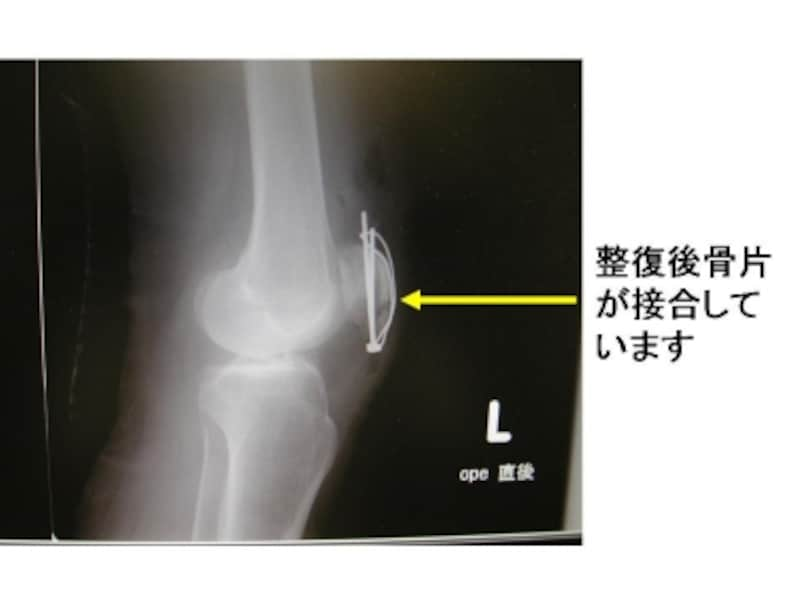

手術で膝蓋骨を金属のワイヤーと棒で固定しました。

膝関節単純X線側面像。離断した骨片がよく接合していることがわかります。

転移がない骨折ですが、方向が横方向の骨折です。

手術で鋼線を使用しました。